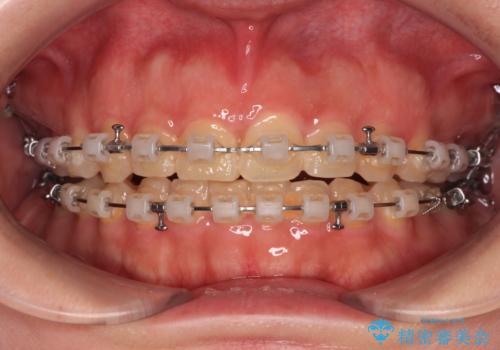

- クリアブラケット

- 3年10ヶ月

口元の突出感は強くなかったため非抜歯矯正での対応となりますが、捻転を改善する際に上顎前歯が前突する可能性があったため、上顎臼歯部にアンカースクリューを使用して、歯列が前方に転位しないようにすることとしました。